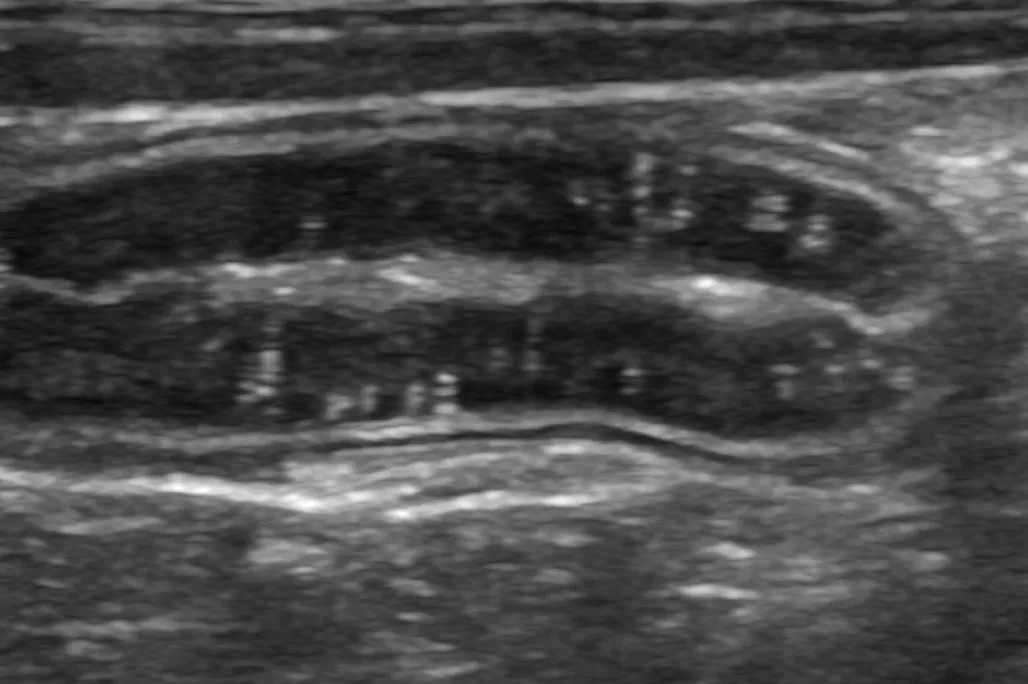

身体検査では軽度の削痩を認めました。血液検査では低アルブミン血症(2.1 g/dl)を認めました。エコー検査では小腸の広範囲でリンパ管拡張を示す白い縦縞のストリエーションサイン(正常な腸には見られない、エコーで映る縞模様 _ 赤矢印)と微量腹水(青矢印)が見られました。

ストリエーションサインは特に空腸で重度にみられ、隣に描出した十二指腸の粘膜層(黒く分厚い層)と比較してかなり白く見えます(黄矢印)。各検査から可能性のある病気を除外し、蛋白漏出性腸症を強く疑いました。全身状態も悪くないため、ご家族と相談し、内視鏡検査を行う前にまずは食事療法の反応性を確認します。